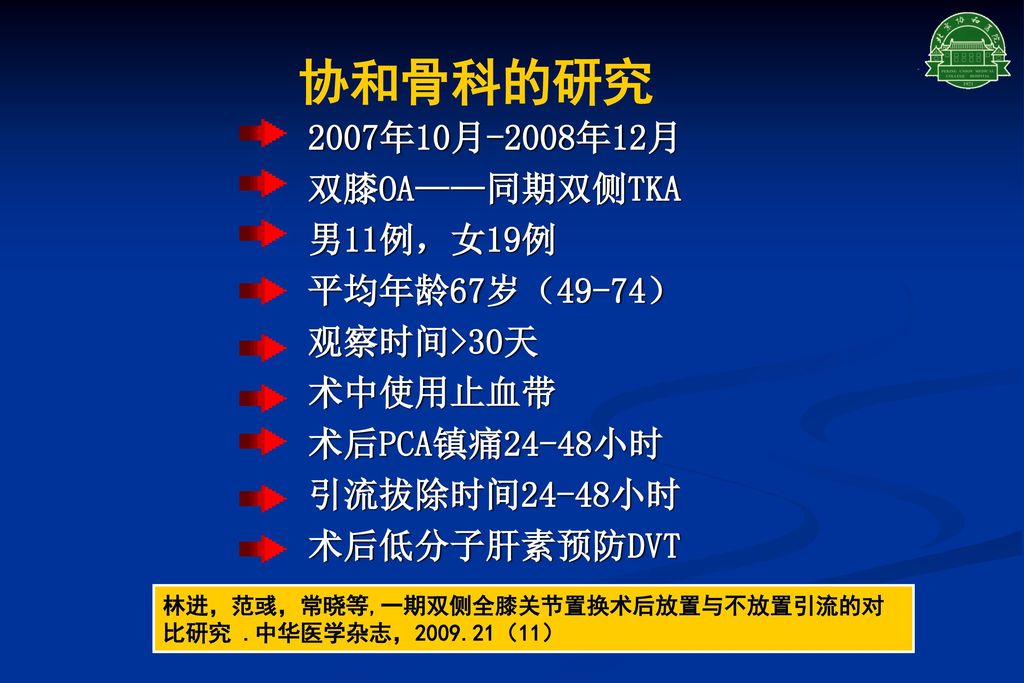

血液管理骨科减少输血的经验分享沈建雄北京协和医院骨科 Ppt Download